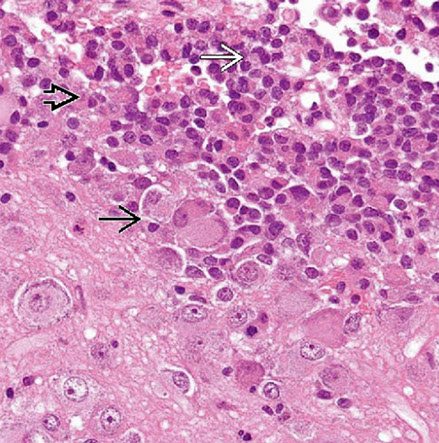

Composite gangliocytoma (black arrow) and sparsely granulated somatotroph adenoma (outline arrow) are shown. Paranuclear fibrous bodies (white arrow) seen in adenoma cells.